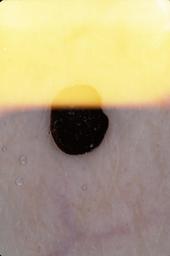

{

"age_approx": 65,

"anatom_site_general": "lower extremity",

"concomitant_biopsy": true,

"dermoscopic_type": "contact non-polarized",

"diagnosis_1": "Benign",

"diagnosis_2": "Hemorrhagic lesions",

"diagnosis_3": "Hemorrhage",

"diagnosis_confirm_type": "histopathology",

"image_type": "dermoscopic",

"lesion_id": "IL_6613464",

"melanocytic": false,

"patient_id": "IP_6628832",

"sex": "female"

}